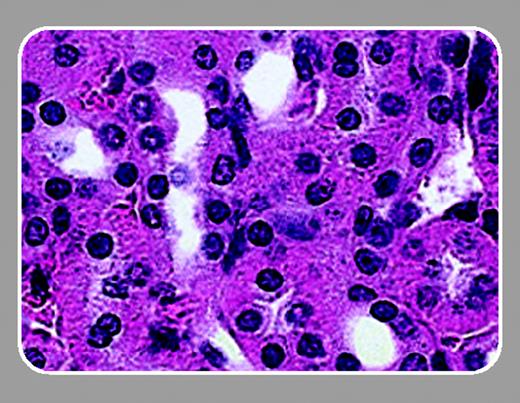

In this issue of Blood, Lavasseur and colleagues (page 4312) have followed up on the original description of successful correction of SCD in the mouse model. Similar to Pawliuk et al,5 Lavasseur et al demonstrate that lentivirus-mediated gene transfer of a modified human β-globin gene could inhibit the sickling of mouse SCD erythrocytes. In addition, they describe significant improvements in all clinical parameters measured, including liver and spleen necrosis and kidney function.